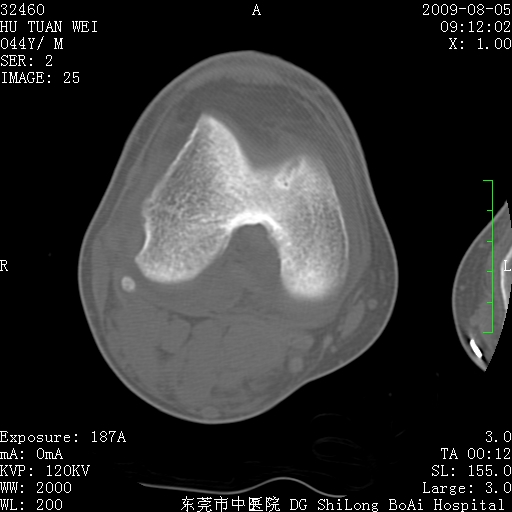

中年男性,膝韧带损伤术前检查!其他病史不清粗,不是我接手病人、且出院了!

1、股骨下段囊状膨胀性病变,边缘硬化明显,内多个残留骨棘呈多房型改变,囊腔密度较高无钙化,膝关节滑膜囊增厚,密度增高,关节腔少量积液。考虑:邻关节囊肿、退变性囊肿(软骨下囊肿)、着色性绒毛结节性滑膜炎、abc、骨巨、良性纤维组织细胞瘤等鉴。虽然年龄偏大,部位于骨端,但有外伤史,本人还是倾向于动脉瘤样骨囊肿(abc)可能性大。邻关节囊肿及软骨下囊肿次之考虑。

2、胫骨髁间棘撕脱骨折,交叉韧带损伤可能;

3、关节退行性改变。

病理结果:色素沉着绒毛结节性滑膜炎

感谢反馈病理结果!本病为慢性关节病变。以关节滑膜高度增生、绒毛结节形成伴含铁血黄素趁着为特点。病因:有炎症、肿瘤、外伤关节出血、代谢障碍、变态反应及感染等学说。增强扫描呈关节腔内单个或多个强化的软组织结节影或滑膜不规则增厚伴关节积液为本病的特征性表现。